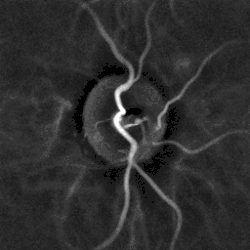

Hypertensive retinopathy with AV nicking and mild vascular tortuosity | |

Hypertensive retinopathy is damage to the retina and retinal circulation due to high blood pressure (i.e. hypertension).

- Arteriolar changes, such as generalized arteriolar narrowing, focal arteriolar narrowing, arteriovenous nicking, changes in the arteriolar wall (arteriosclerosis) and abnormalities at points where arterioles and venules cross. Manifestations of these changes include Copper wire arterioles where the central light reflex occupies most of the width of the arteriole and Silver wire arterioles where the central light reflex occupies all of the width of the arteriole, and "arterio-venular (AV) nicking" or "AV nipping", due to venous constriction and banking.